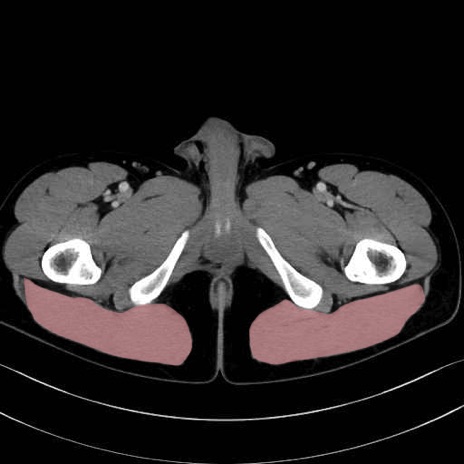

3. 殿部の筋肉(表層・中層・深層)

大殿筋 (Gluteus maximus)